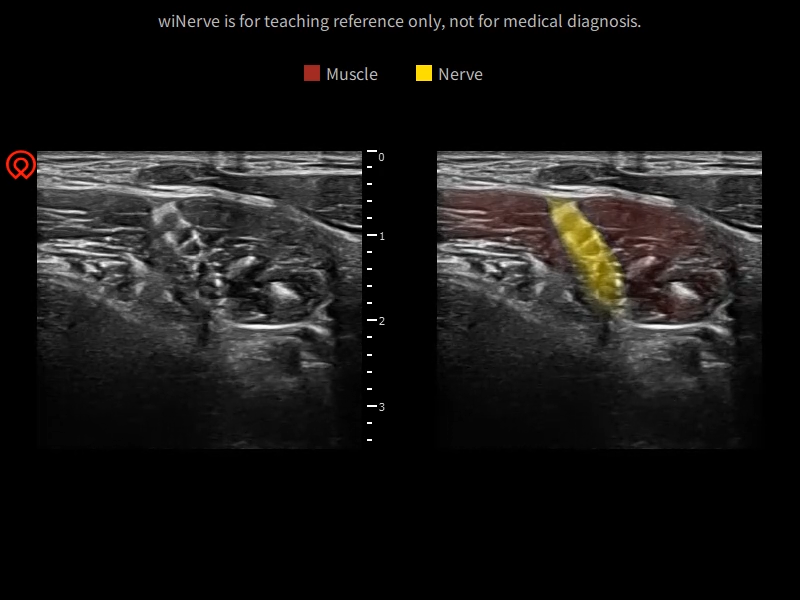

wiNerve - AI Intelligent Nerve Recognition

Real-time Recognition

Cloud Solution

Support Multiple Nerves

Online Guidance